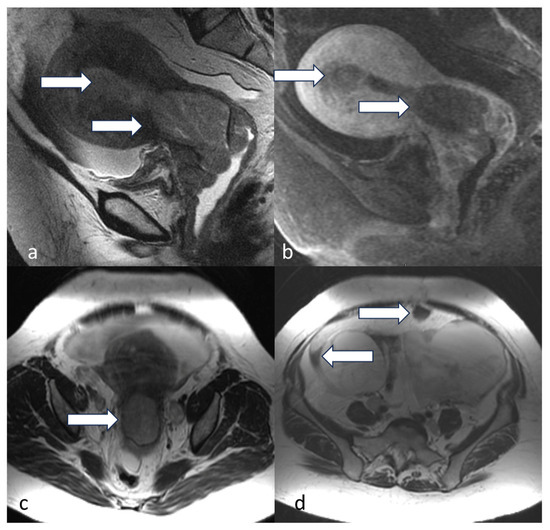

5.3. Magnetic Resonance Imaging (MRI)

4.1. Stage I

4.2. Stage II